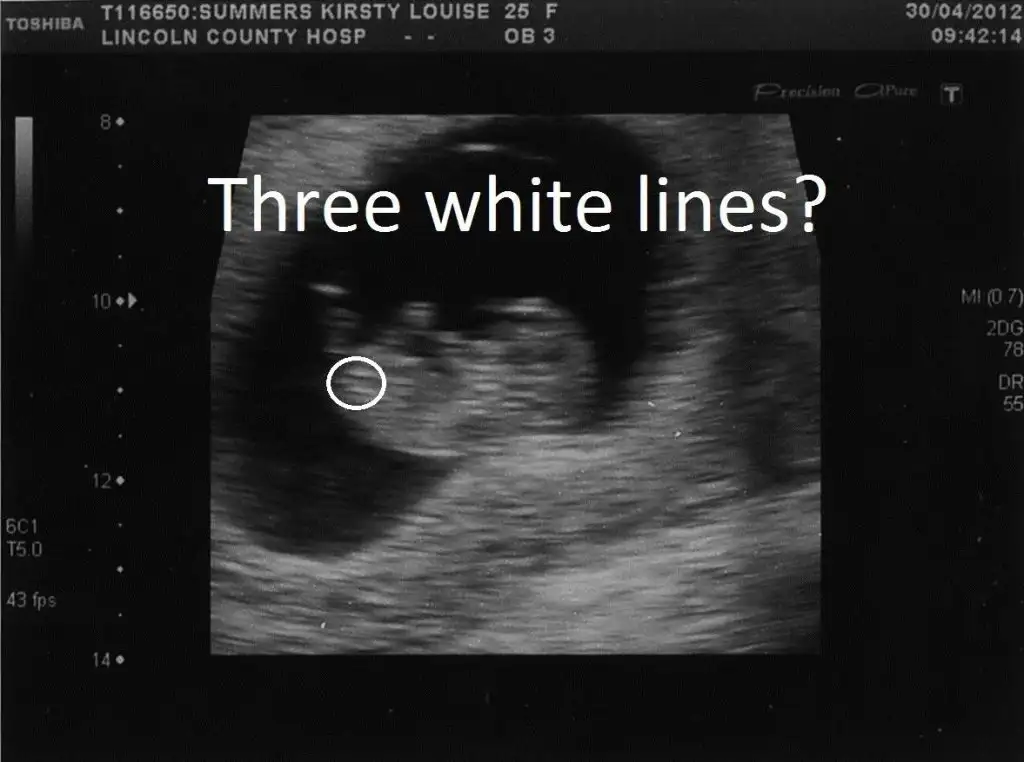

Erkeğe daha çok benzettim ikinci resimden dolayı. Ama kesin diyemem.Kızlar cinsiyet konusunda tahmin alabilirmiyim??Eki Görüntüle 1522208 Eki Görüntüle 1522219

BANA YORUM YOKMU KIZLAR11 + 0 haftalık bebeğim yorum alabilirmiyiz

Henüz nubu oluşmamış bu teori için 12-13 haftalar en ideal zamanlar.

Daha vakit var o zaman dimi canımNubu görünmüyor.